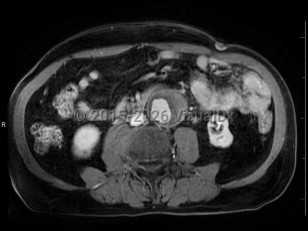

- The aorta diameter is measured from outer wall to outer wall. A common pitfall is the misinterpretation of thrombus with the outer wall of the aorta.

AAA is defined as a focal, full-thickness dilation of the abdominal aorta that is 50% or more of the regular diameter, or 3 cm or larger. The abdominal aorta is retroperitoneal and lies between the diaphragm and aortic bifurcation, with about 80% of aneurysms arising infrarenally. They are most commonly degenerative in patients with atherosclerosis; 5%-10% are inflammatory and are more often symptomatic.